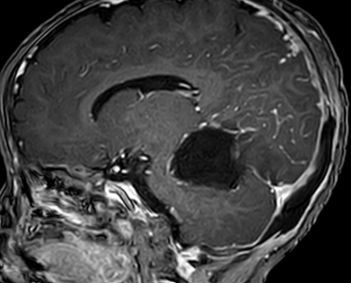

2026年3月3日,由张玉琪院长主刀,经枕下幕上入路小脑幕上、下病变切除术。手术历时4小时,镜下近全切除肿瘤,周围脑干、颅神经及血管保护良好,出血仅100ml。术后患儿转入NICU(新生儿重症监护病房),次日平稳返回普通病房。病理确诊为胚胎性肿瘤,WHO Ⅳ级(世界卫生组织(WHO)根据肿瘤恶性程度划分的最高级别(IV级)的恶性肿瘤)。术后虽康复情况充满挑战,但由医护团队通过中西医结合治疗后顺利恢复健康,并于术后第17天顺利启动第一周期化疗。

脑肿瘤术后2